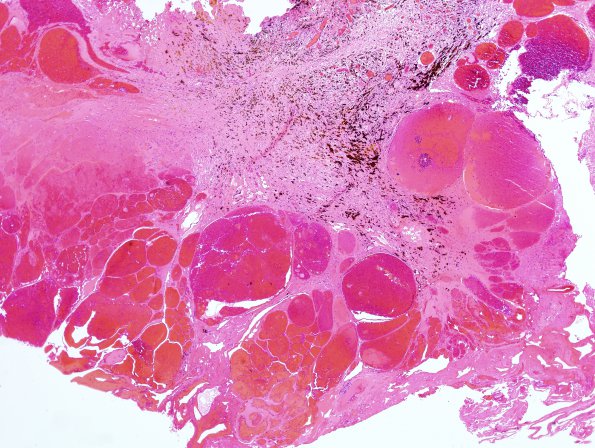

19B2 Cavernous Angioma (Case 19) H&E 3

Higher magnification of an area of image 19B1 (H&E)